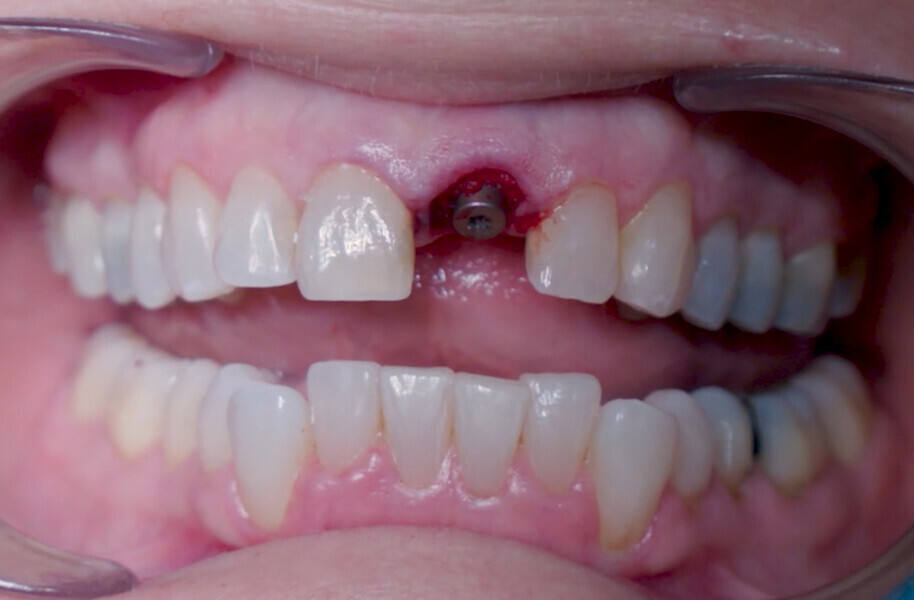

Fig. 12: Final implant position assessment in relation to gingival margins.

Fig. 11: Final implant position assessment.